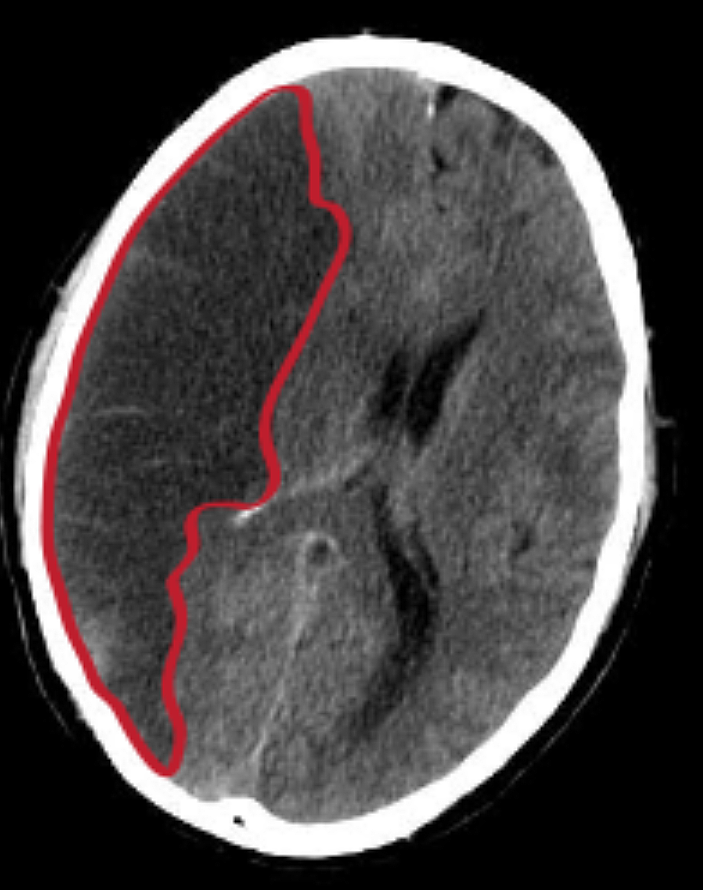

뇌경색은 원인에 따라 뇌혈전증과 뇌색전증으로 구분할 수 있습니다. 뇌혈전증은 뇌혈관 자체에 혈전이 나타나서 혈관이 점차 좁아지다가 막히는 질병입니다. 반면 뇌색적은 심장 등 다른 부위에서 나타난 혈전이 혈관을 타고 올라와서 뇌동맥을 막는 것을 말합니다. 뇌경색은 죽어가는 뇌세포를 살리기 위해 1분 1초가 중요한 응급질환입니다. 증상이 발생한 후 3시간 이내로 치료를 해야되서 초기 증상이 나타났다면 즉시 병원에 방문해야 합니다.

대표적인 원인은 고혈압입니다. 뇌경색 환자의 60% 이상이 고혈압을 가지고 있습니다. 그다음 대표 원인은 당뇨병으로 전체 환자의 약 30%에서 발생합니다. 고혈압, 당뇨병, 이상지질혈증 등의 만성질환을 앓고 있는 분들은 뇌경색이 발생할 위험을 안고 있는겁니다. 이외에도 관상동맥질환, 부정맥 등 심장질환이 있는 경우에도 뇌경색이 발생할 위험이 있습니다. 또한 흡연, 비만, 음주 등의 생활 습관들도 뇌경색 발병 위험을 높일 수 있습니다.뇌경색뿐 아니라 뇌출혈 뇌졸중등 여러 뇌질환이 있으니 꼭 참고하시기 바랍니다.